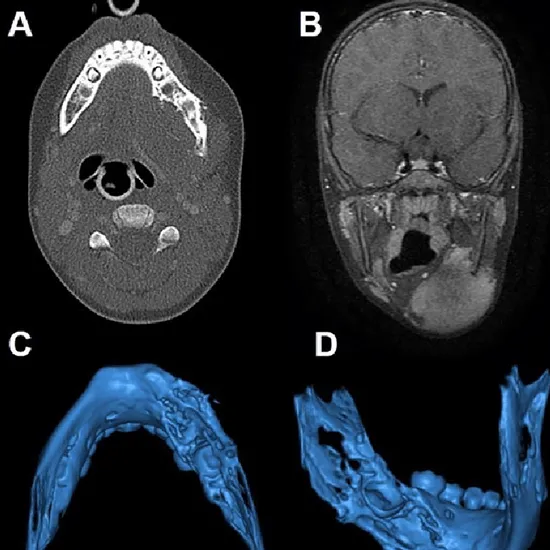

MRI Screening of the mandible is a highly accurate examination in detecting the extension of oral cancer in surrounding soft tissues. It helps detect mandible bone invasion and restriction in movement.

The MRI Screening of the mandible is recommended for the patient with a diagnosis of oral cancer. It helps in detecting whether oral cancer has spread to the soft tissues of the brain, head, and neck. It is also recommended when a doctor is unable to diagnose the problem clearly with other imaging procedure and need further investigation.